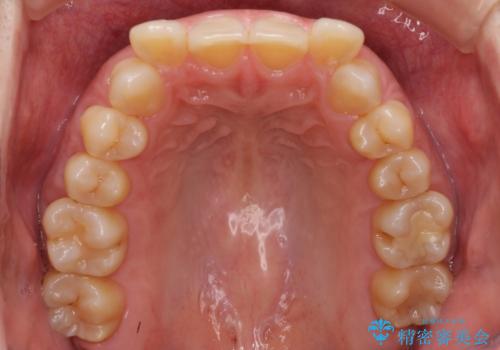

下顎2前歯の欠損 インビザラインによる抜歯矯正

- 下顎前歯欠損による歯列不正を気にして来院された患者様です。

下顎の歯列が小さく、下顎前歯が隠れてしまう過蓋咬合(ディープバイト)であったため、

マウスピースでの抜歯矯正特有の抜歯スペースに向かって奥歯が傾斜する動きが顕著に表れ、ディープバイトは改善されませんでした。

前歯のみが強く接触し、奥歯で咬めない期間も続いたため、ワイヤー装置などを補助的に使用し、何とか終了させることができました。